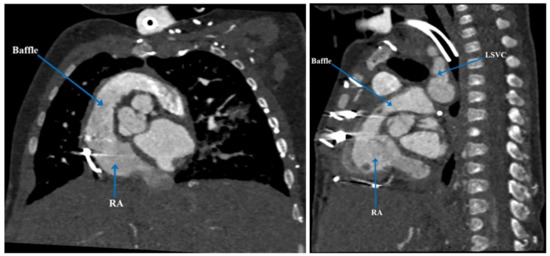

| Present case [6] | Heterotaxy syndrome with partial LPA sling, partial AV canal with a common atrium, atrial situs ambiguous, interrupted IVC, VSD, and PDA | 5 months | PDA occlusion, clipping and division of the anomalous LPA | Defined complex anatomy and surgical plan for biventricular repair | Biventricular repair |